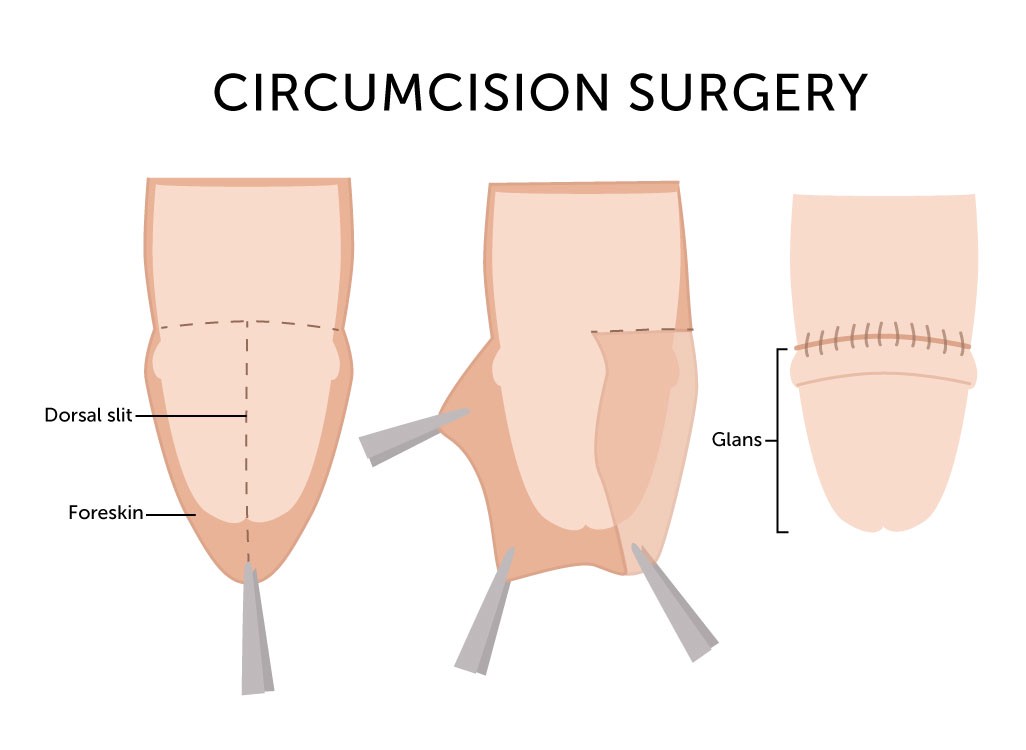

Overview

Package includes:

Days in hospital : 1 to 2 Days (For patient and one attendant)

Days in hotel : 3 Days (For patient and one attendant)

Room type in hospital : Shared

Room type in hotel : Private

Hotel category: Standard

Value added benefits of the Circumcision: